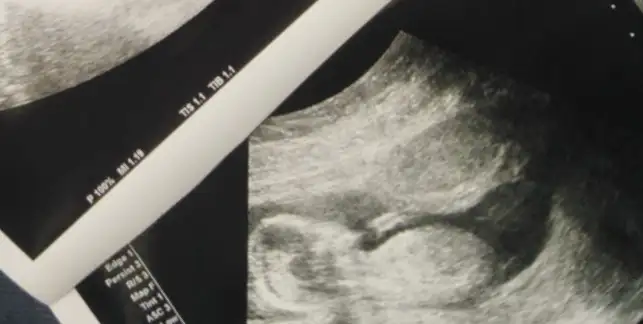

Buda 11 haftalık görüntüsü arkadaşlar. Tahmimde bulununnnn çatlicamm